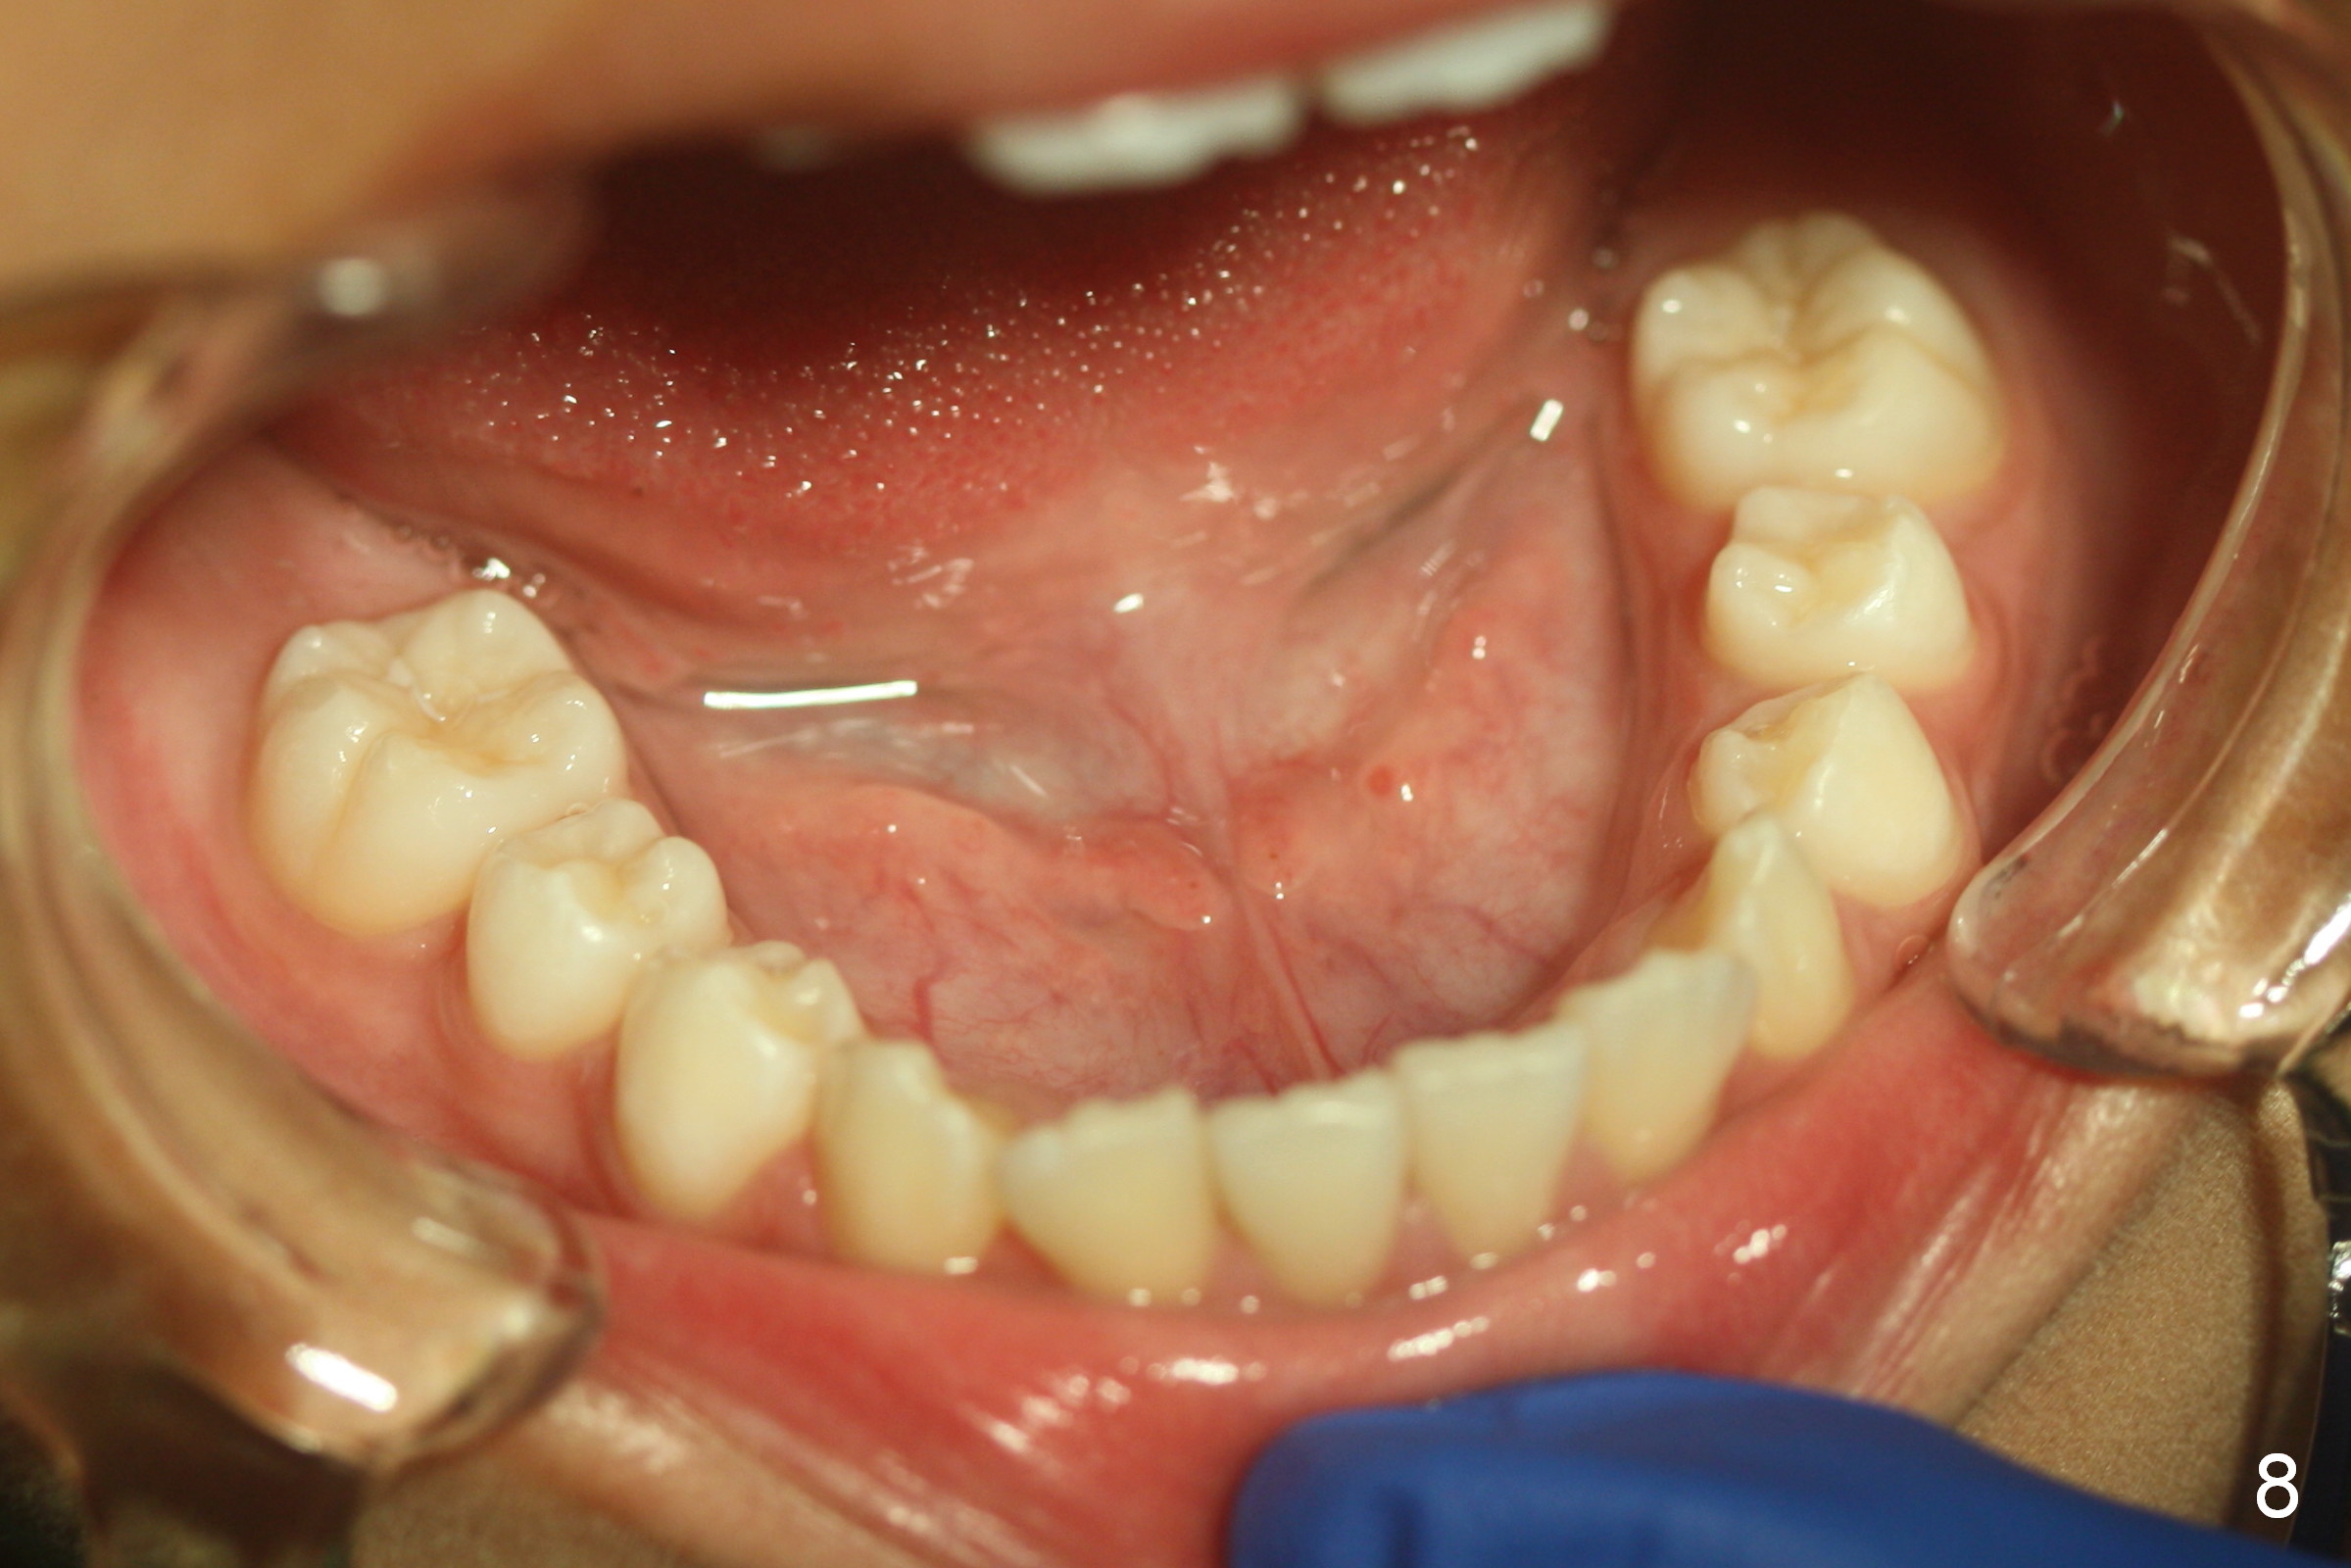

A 11-year-old boy has history of asthma. His father has sleep apnea with similar Class II malocclusion. Pan was taken for the boy 3 years ago (Fig.1). His mother wants to have orthodontic treatment as early as possible, because of protrusive upper anterior teeth. The dentition is permanent except the upper left canine and 1st molar (Fig.7,10,12,13 C, D). It appears that there is bilateral Class II occlusion at canine by half a tooth (Fig.9-12). The malocclusion and facial profile can be easily corrected with extraction of the upper 1st bicuspids.